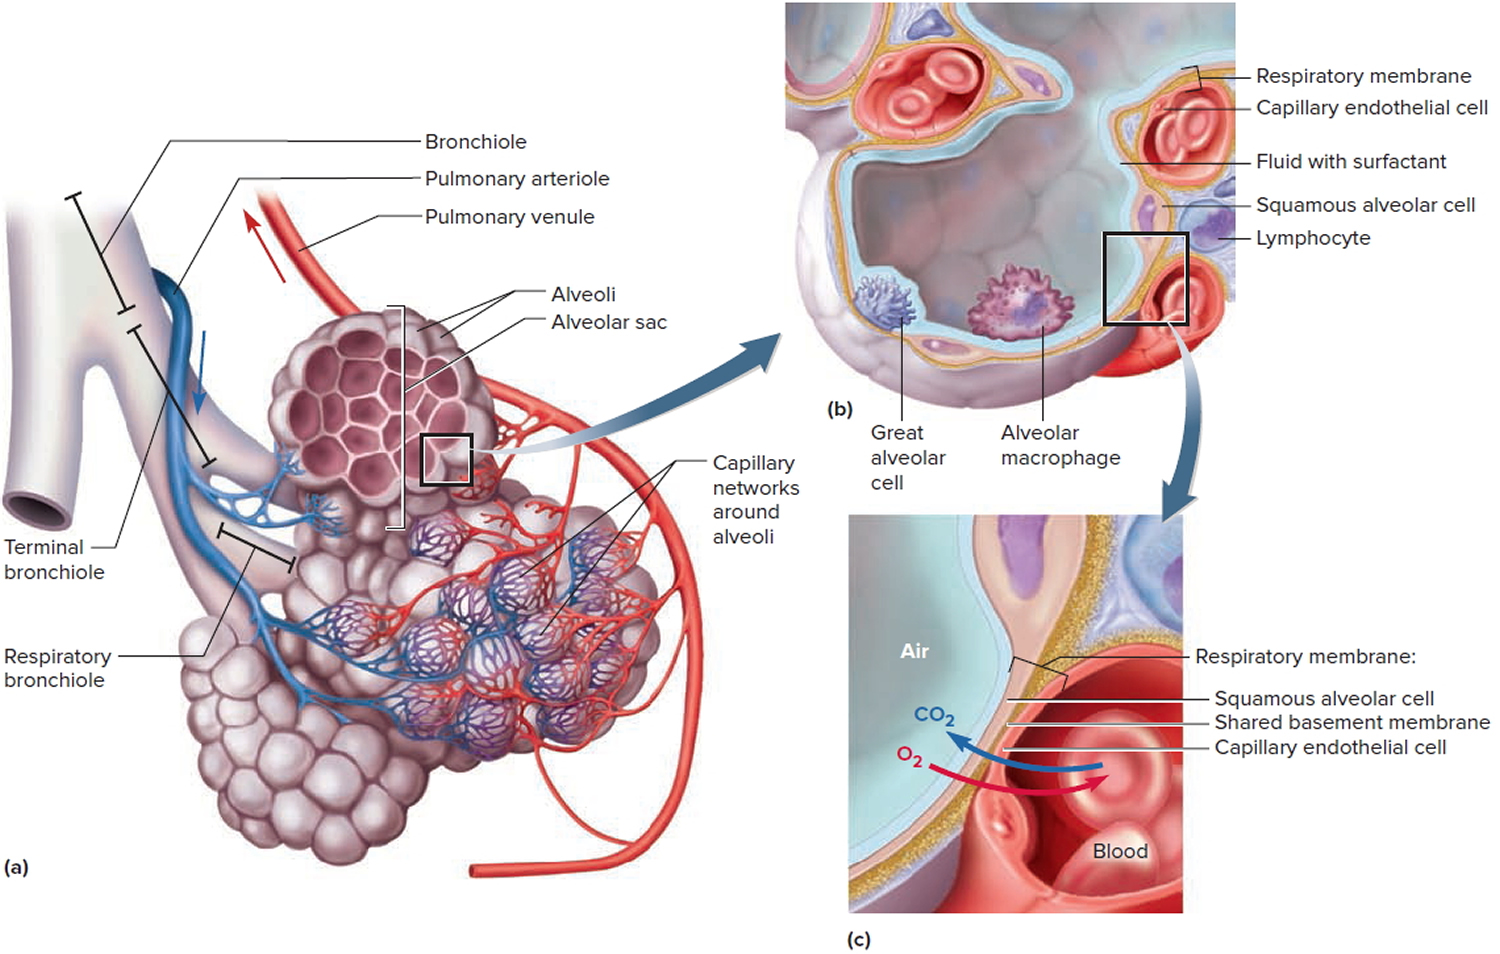

Organs And Structures Of The Respiratory System | Anatomy And Physiology II

courses.lumenlearning.com

courses.lumenlearning.com

respiratory alveolar system bronchioles sacs structures exchange figure division organs lungs zone pulmonary anatomy occurs lead gas where blood